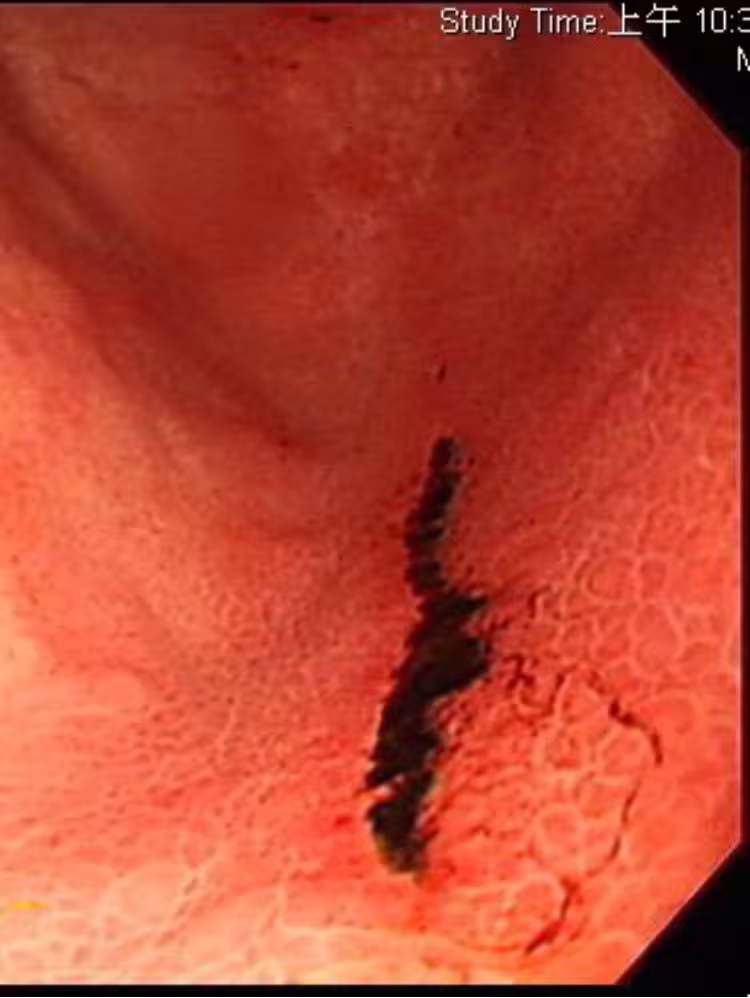

肚子爆痛拉黑糞!他生活超養身「胃竟冒5潰瘍」全爛光!醫一問才知「每天都喝1飲料」驚呼:酸度爆表!

經過醫師的精密檢查,發現這名40多歲男子的胃竟有多達5處的潰爛傷口,某些嚴重的部位甚至有出血情況,可見病情嚴重。 但離奇的是,平時他並沒有不良習慣,用餐也相對清淡、規律,更沒有喝咖啡、茶、果汁等飲品,甚至連零食都沒有吃,照理來說並不會出現那麼可怕的潰瘍傷口。